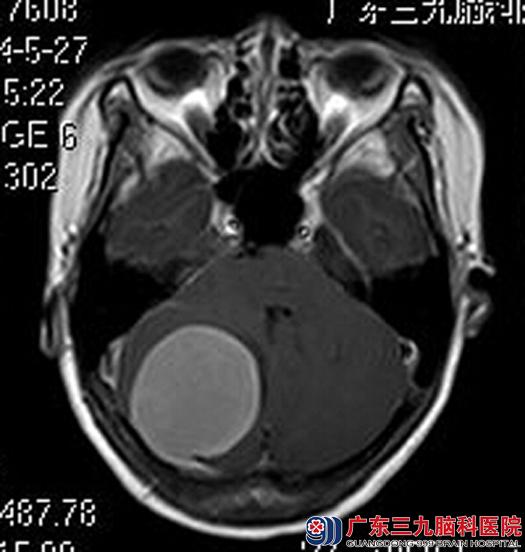

为进一步查找原因,她来到了广东三九脑科医院。头颅MRI检查提示:后颅窝右侧小脑半球区示一类圆形的占位性病变,大小约4.3cm×4.7cm×4.5cm,病变上缘与后缘紧贴邻近硬脑膜,邻近脑组织受压明显移位,考虑脑膜瘤可能性大。

手术前